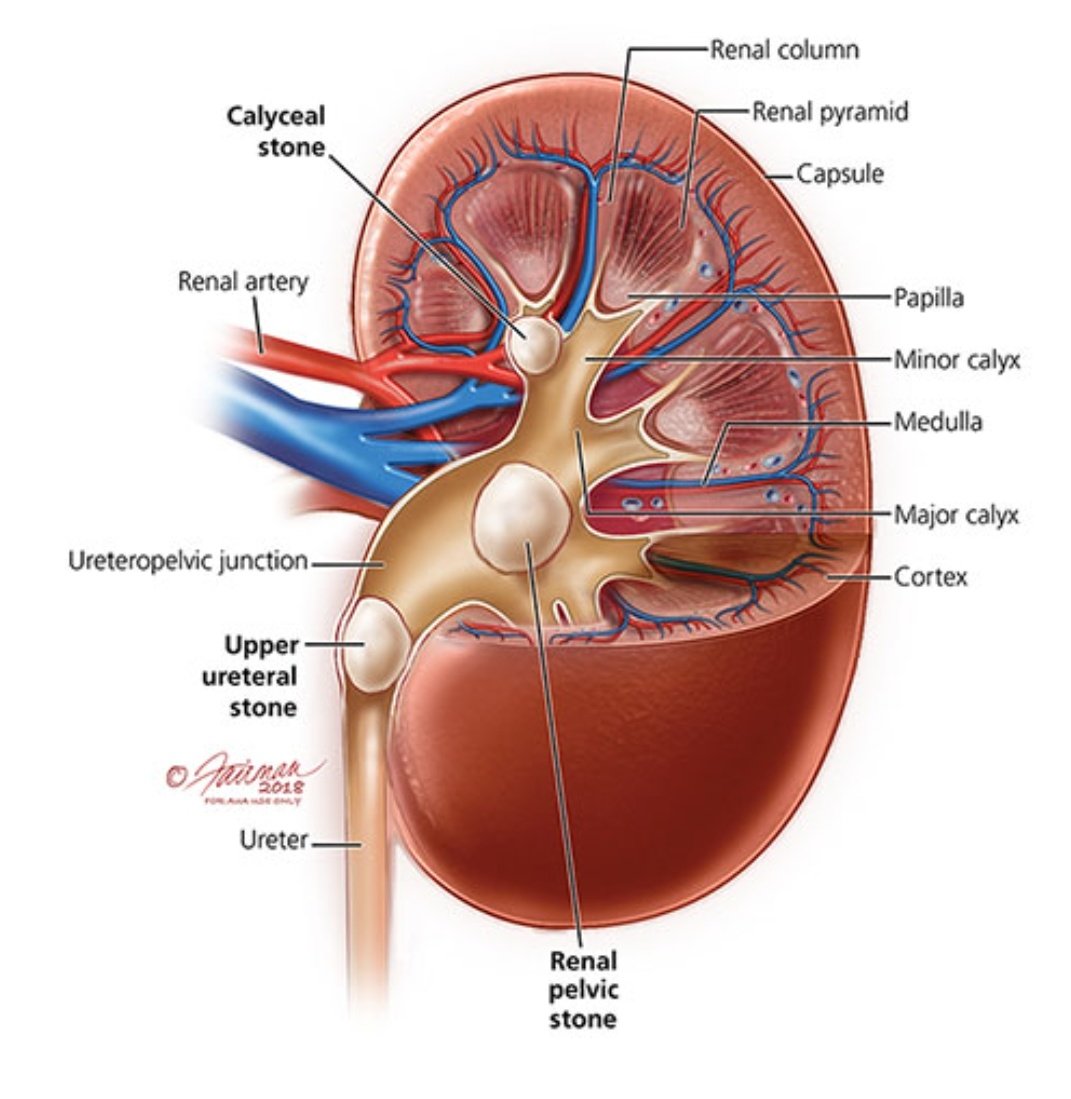

📌اليوم بتكلم عن حصوات الكلى والمسالك البولية ..

⛔اسباب تكوين الحصوات وليه أحنا من اكثر الدول الي تعاني من الحصوات.

⛔مضاعفات ترك الحصوات وعدم علاجها.

⛔اسباب تكوين الحصوات وليه أحنا من اكثر الدول الي تعاني من الحصوات.

⛔مضاعفات ترك الحصوات وعدم علاجها.